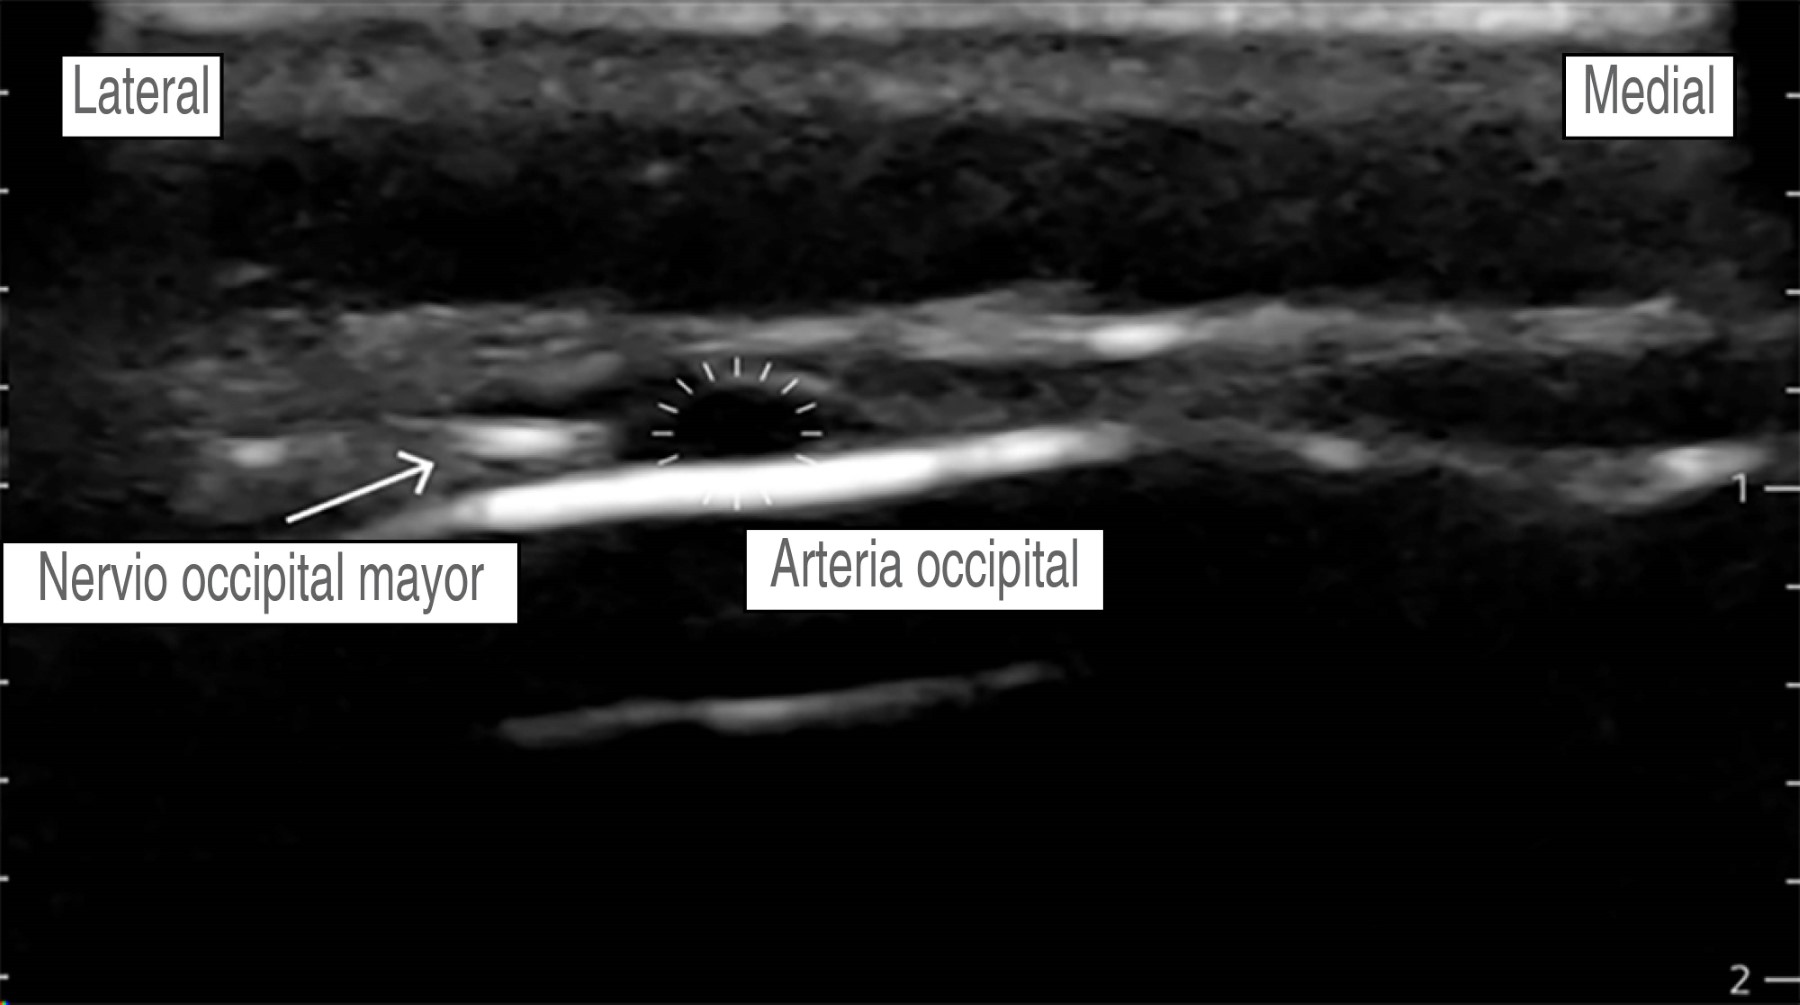

Hombre de 56 años, con diagnóstico de meningioma de la convexidad frontal, con un estado físico de la American Society of Anesthesiologists (ASA) II. Hipertensión arterial esencial en tratamiento regular con losartán 50 mg VO cada 24 horas, sin otros antecedentes. Peso: 87 kg, talla: 1.70 m. Presenta un cuadro clínico de tres meses de evolución caracterizado por cefalea holocraneana, trastornos del comportamiento (apatía, falta de motivación, indiferencia) sin datos de focalización neurológica. La imagen de resonancia magnética muestra una tumoración frontoparietal derecha de 8.2 × 5.1 cm que realza al contraste de forma homogénea, con efecto de masa significativo y desviación de la línea media de 13 mm. Ingresa a sala quirúrgica para craneotomía bifrontal y resección tumoral guiada por neuronavegación. En la sala quirúrgica bajo monitorización invasiva y anestesia total intravenosa con remifentanilo (0.15-0.2 μg/kg/min), propofol (90-120 μg/kg/min), lidocaína (1-2 mg/kg/h) y después de asegurar la vía aérea colocamos un bloqueo de escalpe guiado por USG. Se utilizó una sonda de USG lineal (10 MHz). Nervio supraorbitario y supratroclear: en situación transversal, colocamos la sonda en el hueso frontal sobre el reborde orbitario superior identificando el agujero supraorbitario (muesca). Con técnica en plano, la inyección es superficial al foramen (evitando la administración dentro del foramen), con un volumen de 1.5 mL de anestésico local, para asegurar una cobertura adecuada al nervio supratroclear colocamos otra inyección medial al supraorbitario de 1.5 mL de AL, visualizando su extensión bajo USG. No logramos identificar la arteria supraorbitaria (Figura 2). Nervio cigomático-temporal: colocamos el transductor en un plano coronal, sobre el límite anterior de la fosa temporal, posterior a la apófisis frontal del hueso cigomático, lo que nos deja visualizar tres estructuras: fascia temporal, músculo temporal y hueso temporal, colocamos dos inyecciones de 1.5 mL de AL, en dos puntos de referencia: el hueso temporal (profundo) y la fascia temporal superficial (Figura 3). Nervio auriculotemporal: en el mismo plano facial que el nervio anterior, colocando el transductor en sentido transversal entre el canto lateral del ojo y el trago, identificamos la arteria temporal superficial; el nervio corre en el mismo plano facial que la arteria y lo bloqueamos con 2 mL de AL, evitando la punción vascular (Figura 4). Nervio occipital mayor: colocamos la sonda de USG paralela a una línea que conecta el inión y la mastoides logrando identificar a la arteria occipital junto al nervio. Con inyección en plano utilizamos 2.0 mL de AL (Figura 5). Nervio auricular mayor y occipital menor: bloqueamos ambos nervios a través de un bloqueo de plexo cervical superficial, colocando la sonda transversal sobre la cara lateral del cuello, ubicando el borde posterior del músculo esternocleidomastoideo (ECM) en un punto medio entre la mastoides y la clavícula identificando el plexo como pequeños nódulos hipoecoicos profundos al borde posterior del ECM, el nervio auricular mayor se puede ver comúnmente sobre el músculo ECM. Con técnica en plano la inyección se realizó detrás del ECM, superficial a la fascia prevertebral con un volumen de 5 mL de AL (Figura 6). El bloqueo se realizó de forma bilateral utilizando 28 mL de bupivacaína isobárica a 0.5%, empleando un tiempo de 30 min, se evitó de forma efectiva la respuesta hemodinámica al pinchado, sin necesidad de aumentar la dosis de opioide, o requerir infiltración del área de colocación del pincho, se complementó la analgesia multimodal con paracetamol 1 g IV + ketoprofeno 100 mg IV, no se requirieron rescates de opioide en las 48 horas posteriores y hasta el egreso, se realizó una resección tumoral de 100% sin secuelas neurológicas, no se presentaron complicaciones asociadas al bloqueo de escalpe (punción vascular o déficit nervioso).

Figura 5

Figura 6